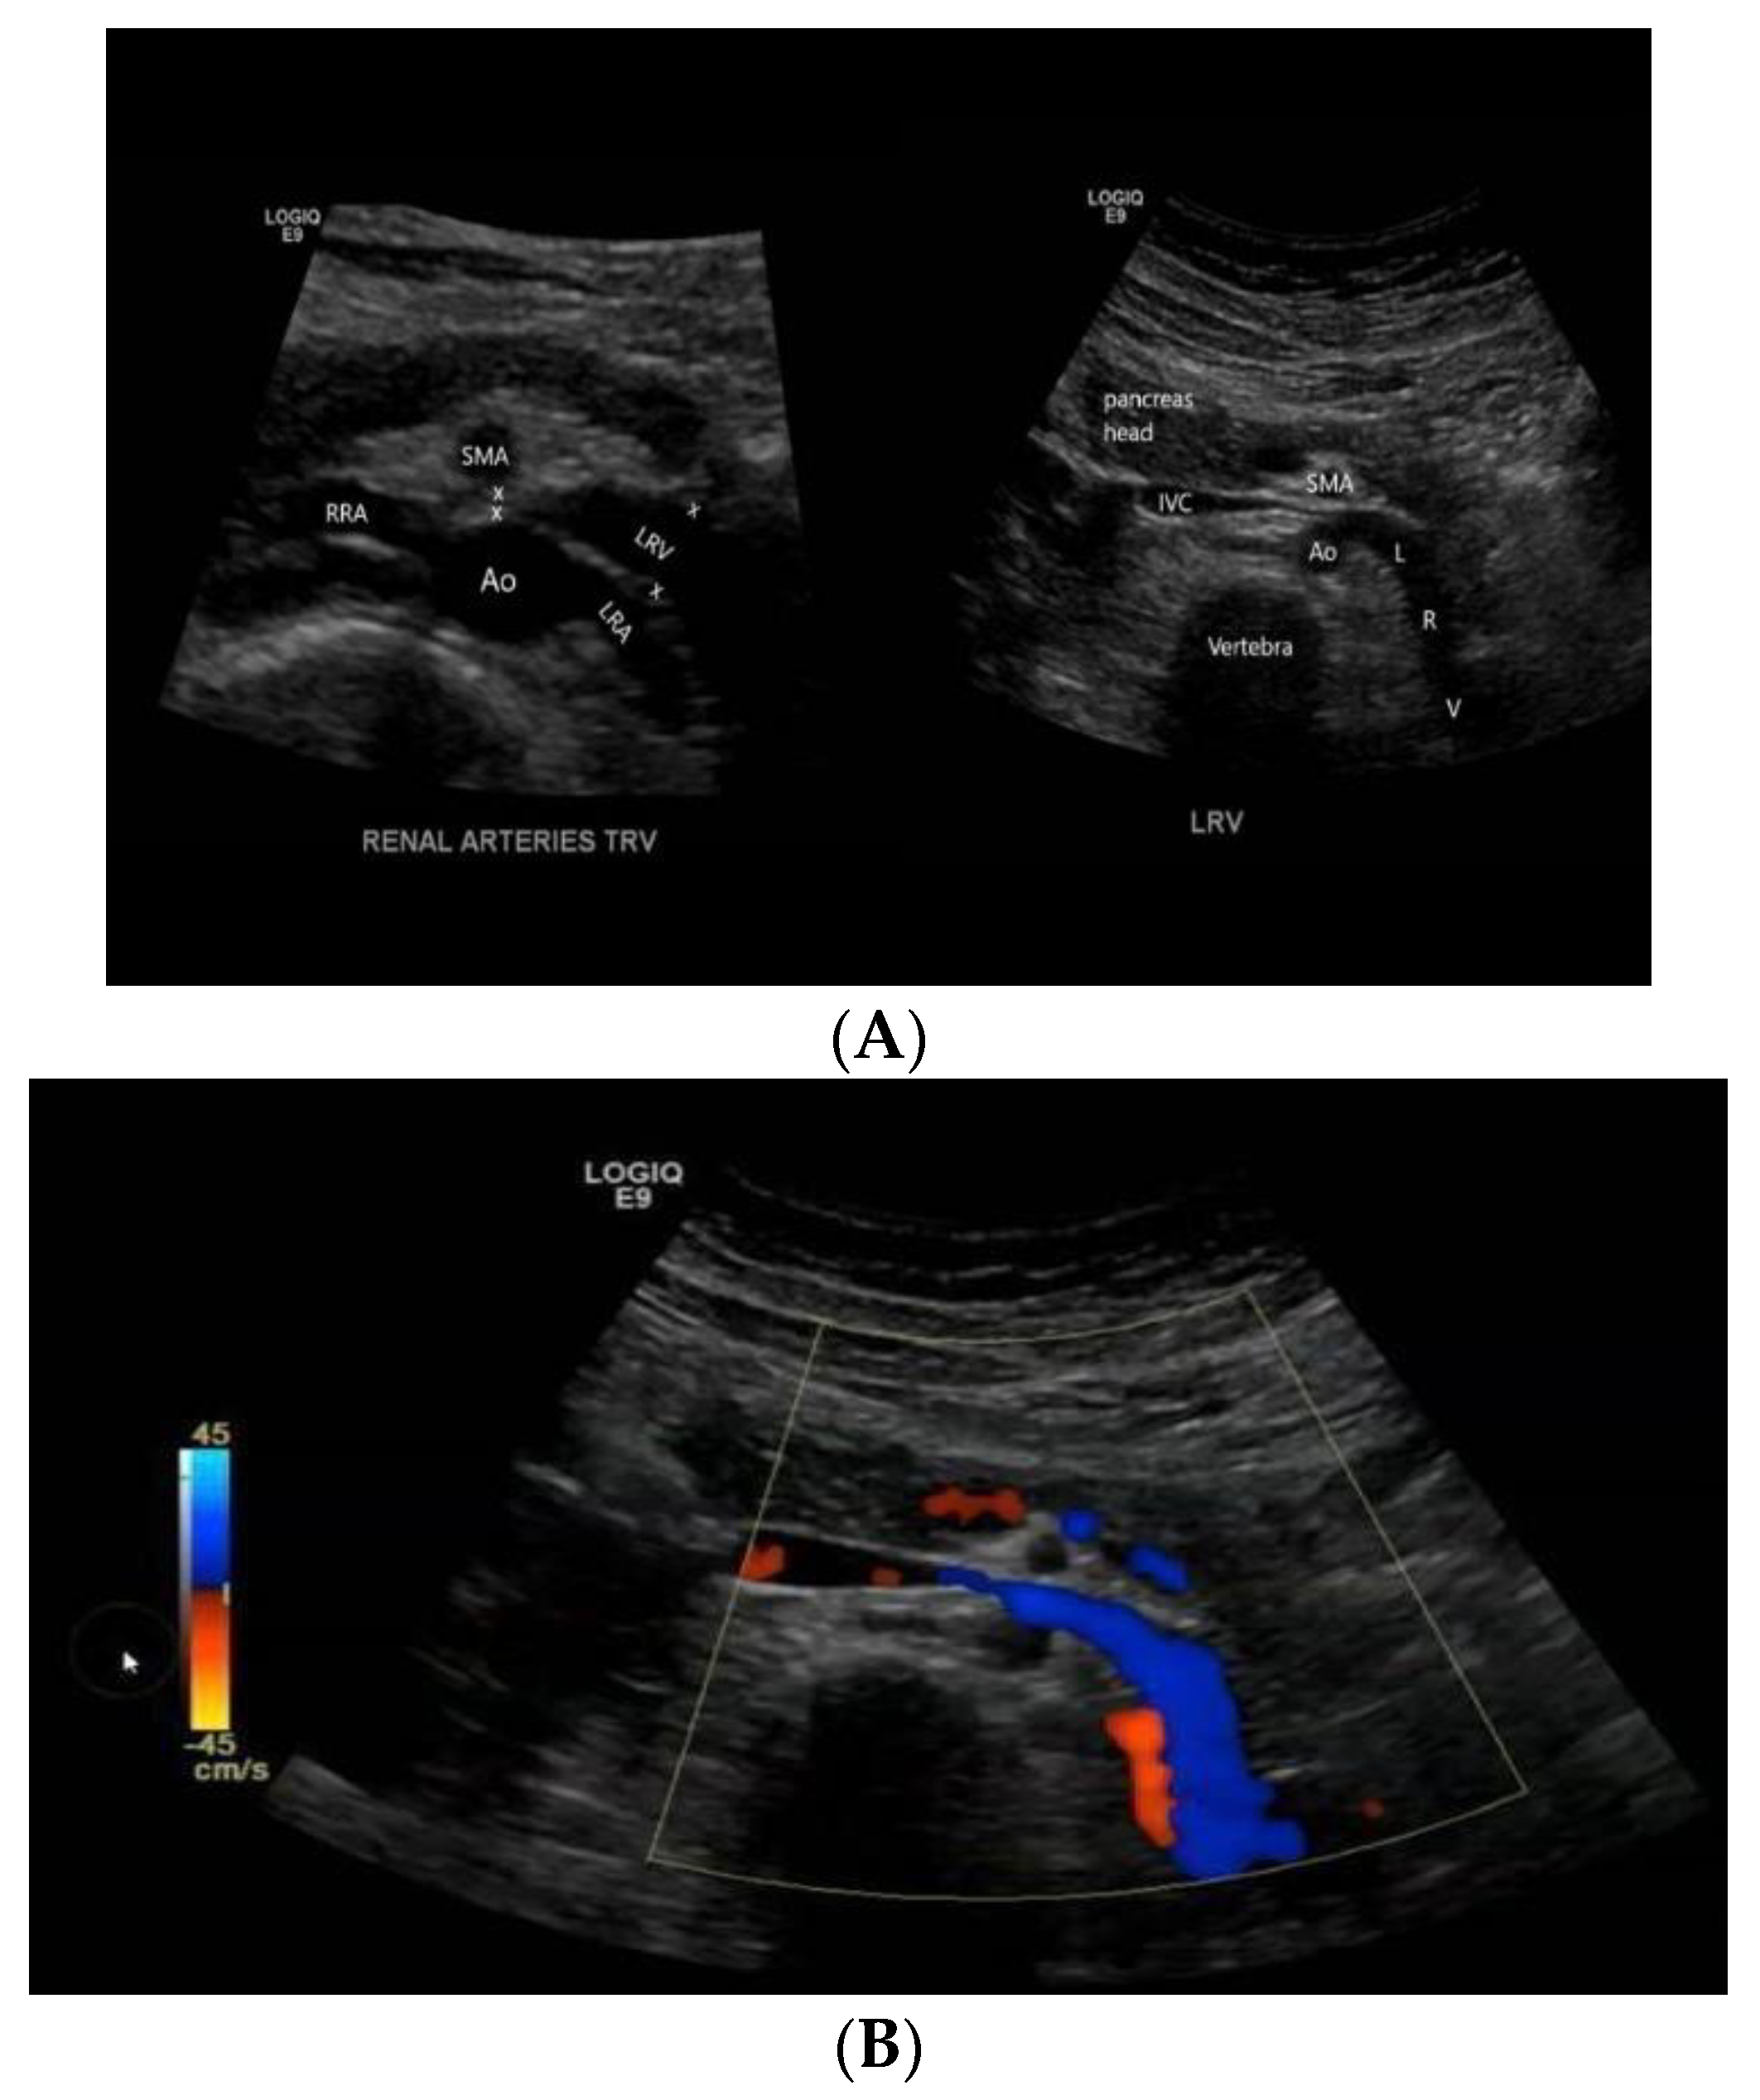

- Kim, S.H.; Cho, S.W.; Kim, H.D.; Chung, J.W.; Park, J.H.; Han, M.C. Nutcracker syndrome: Diagnosis with Doppler US. Radiology 1996, 198, 93–97. [Google Scholar] [CrossRef]

- Kim, S.H.; Doppler, U.S. CT Diagnosis of Nutcracker Syndrome. Korean J. Radiol. 2019, 20, 1627–1637. [Google Scholar] [CrossRef]

- Cheon, J.E.; Kim, W.S.; Kim, I.O.; Kim, S.H.; Yeon, K.M.; Ha, I.S.; Cheong, H.I.; Choi, Y. Nutcracker syndrome in children with gross haematuria: Doppler sonographic evaluation of the left renal vein. Pediatr. Radiol. 2006, 36, 682–686. [Google Scholar] [CrossRef] [PubMed]

- Nalcacioglu, H.; Ceyhan Bilgici, M.; Tekcan, D.; Genc, G.; Bostanci, Y.; Yakupoglu, Y.K.; Sarikaya, S.; Ozkaya, O. Nutcracker Syndrome in Children: Role of Doppler Ultrasonographic Indices in Detecting the Pattern of Symptoms. J. Clin. Med. 2018, 7, 214. [Google Scholar] [CrossRef] [PubMed]

- Shin, J.I.; Park, J.M.; Lee, J.S.; Kim, M.J. Doppler ultrasonographic indices in diagnosing nutcracker syndrome in children. Pediatr. Nephrol. 2007, 22, 409–413. [Google Scholar] [CrossRef]

- Takahashi, Y.; Sano, A.; Matsuo, M. An ultrasonographic classification for diverse clinical symptoms of pediatric nutcracker phenomenon. Clin. Nephrol. 2005, 64, 47–54. [Google Scholar] [CrossRef]